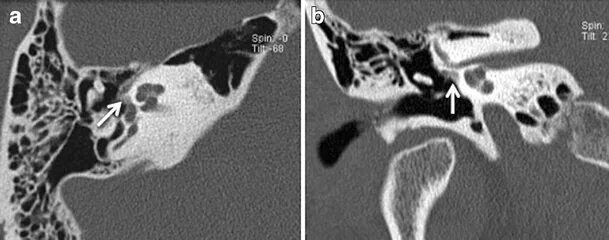

Кохлеарный отосклероз